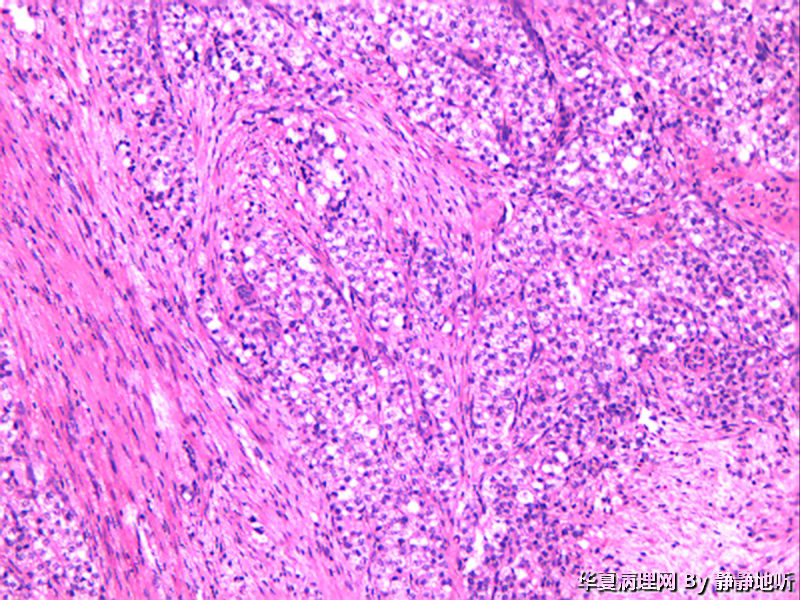

• 骶韧带肿物图1

图1

女性 52岁,盆腔骶韧带肿物。肿瘤球形,直径约2.5厘米,表面光滑,切面结节状,灰粉色。镜下见大量上皮细胞巢,间质为平滑肌。免疫组化:Vimentin +   SMA梭形细胞+  EMA-   CD10-

上级医院做免疫组化:CK+ EMA+  Vimentin +  s-100 弱+  p63-   SMA血管+    CD34 血管+  HMB-45 +  Melanoma+   desmin +   ki-67约20%

会诊意见:低度恶性PEComa